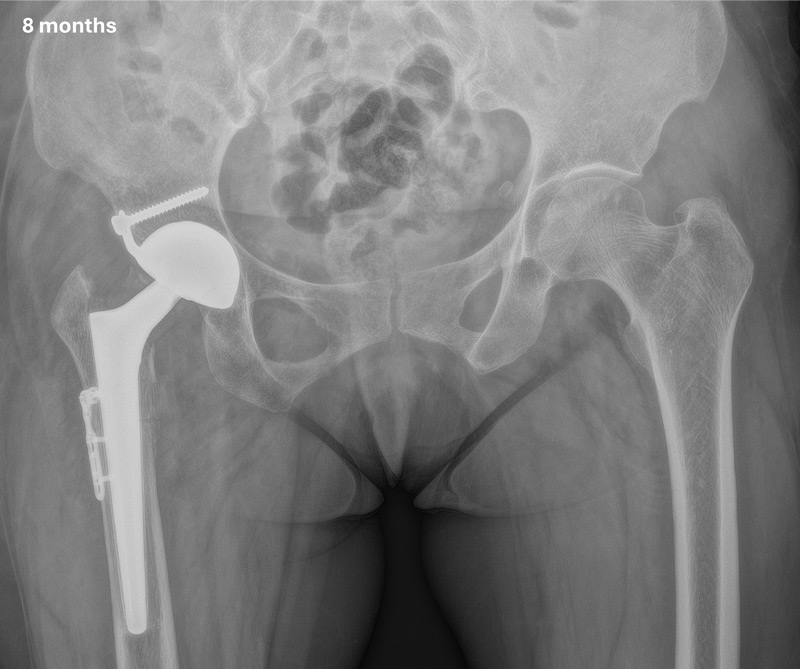

In this case, a total hip replacement was done through an extended anterior approach. A dual mobility cup was impacted in the true acetabulum and a subtrochanteric osteotomy, fixed with a LCP small foot plate, was performed in order to restore the lower limb length reducing the risk of nerve injury. Psoas and adductor tenonotmy was also performed.

Post-operative X-rays

Management of a hip dysplasia in a middle-aged woman: Post-operative X-rays

Clinical aspect at 8 months